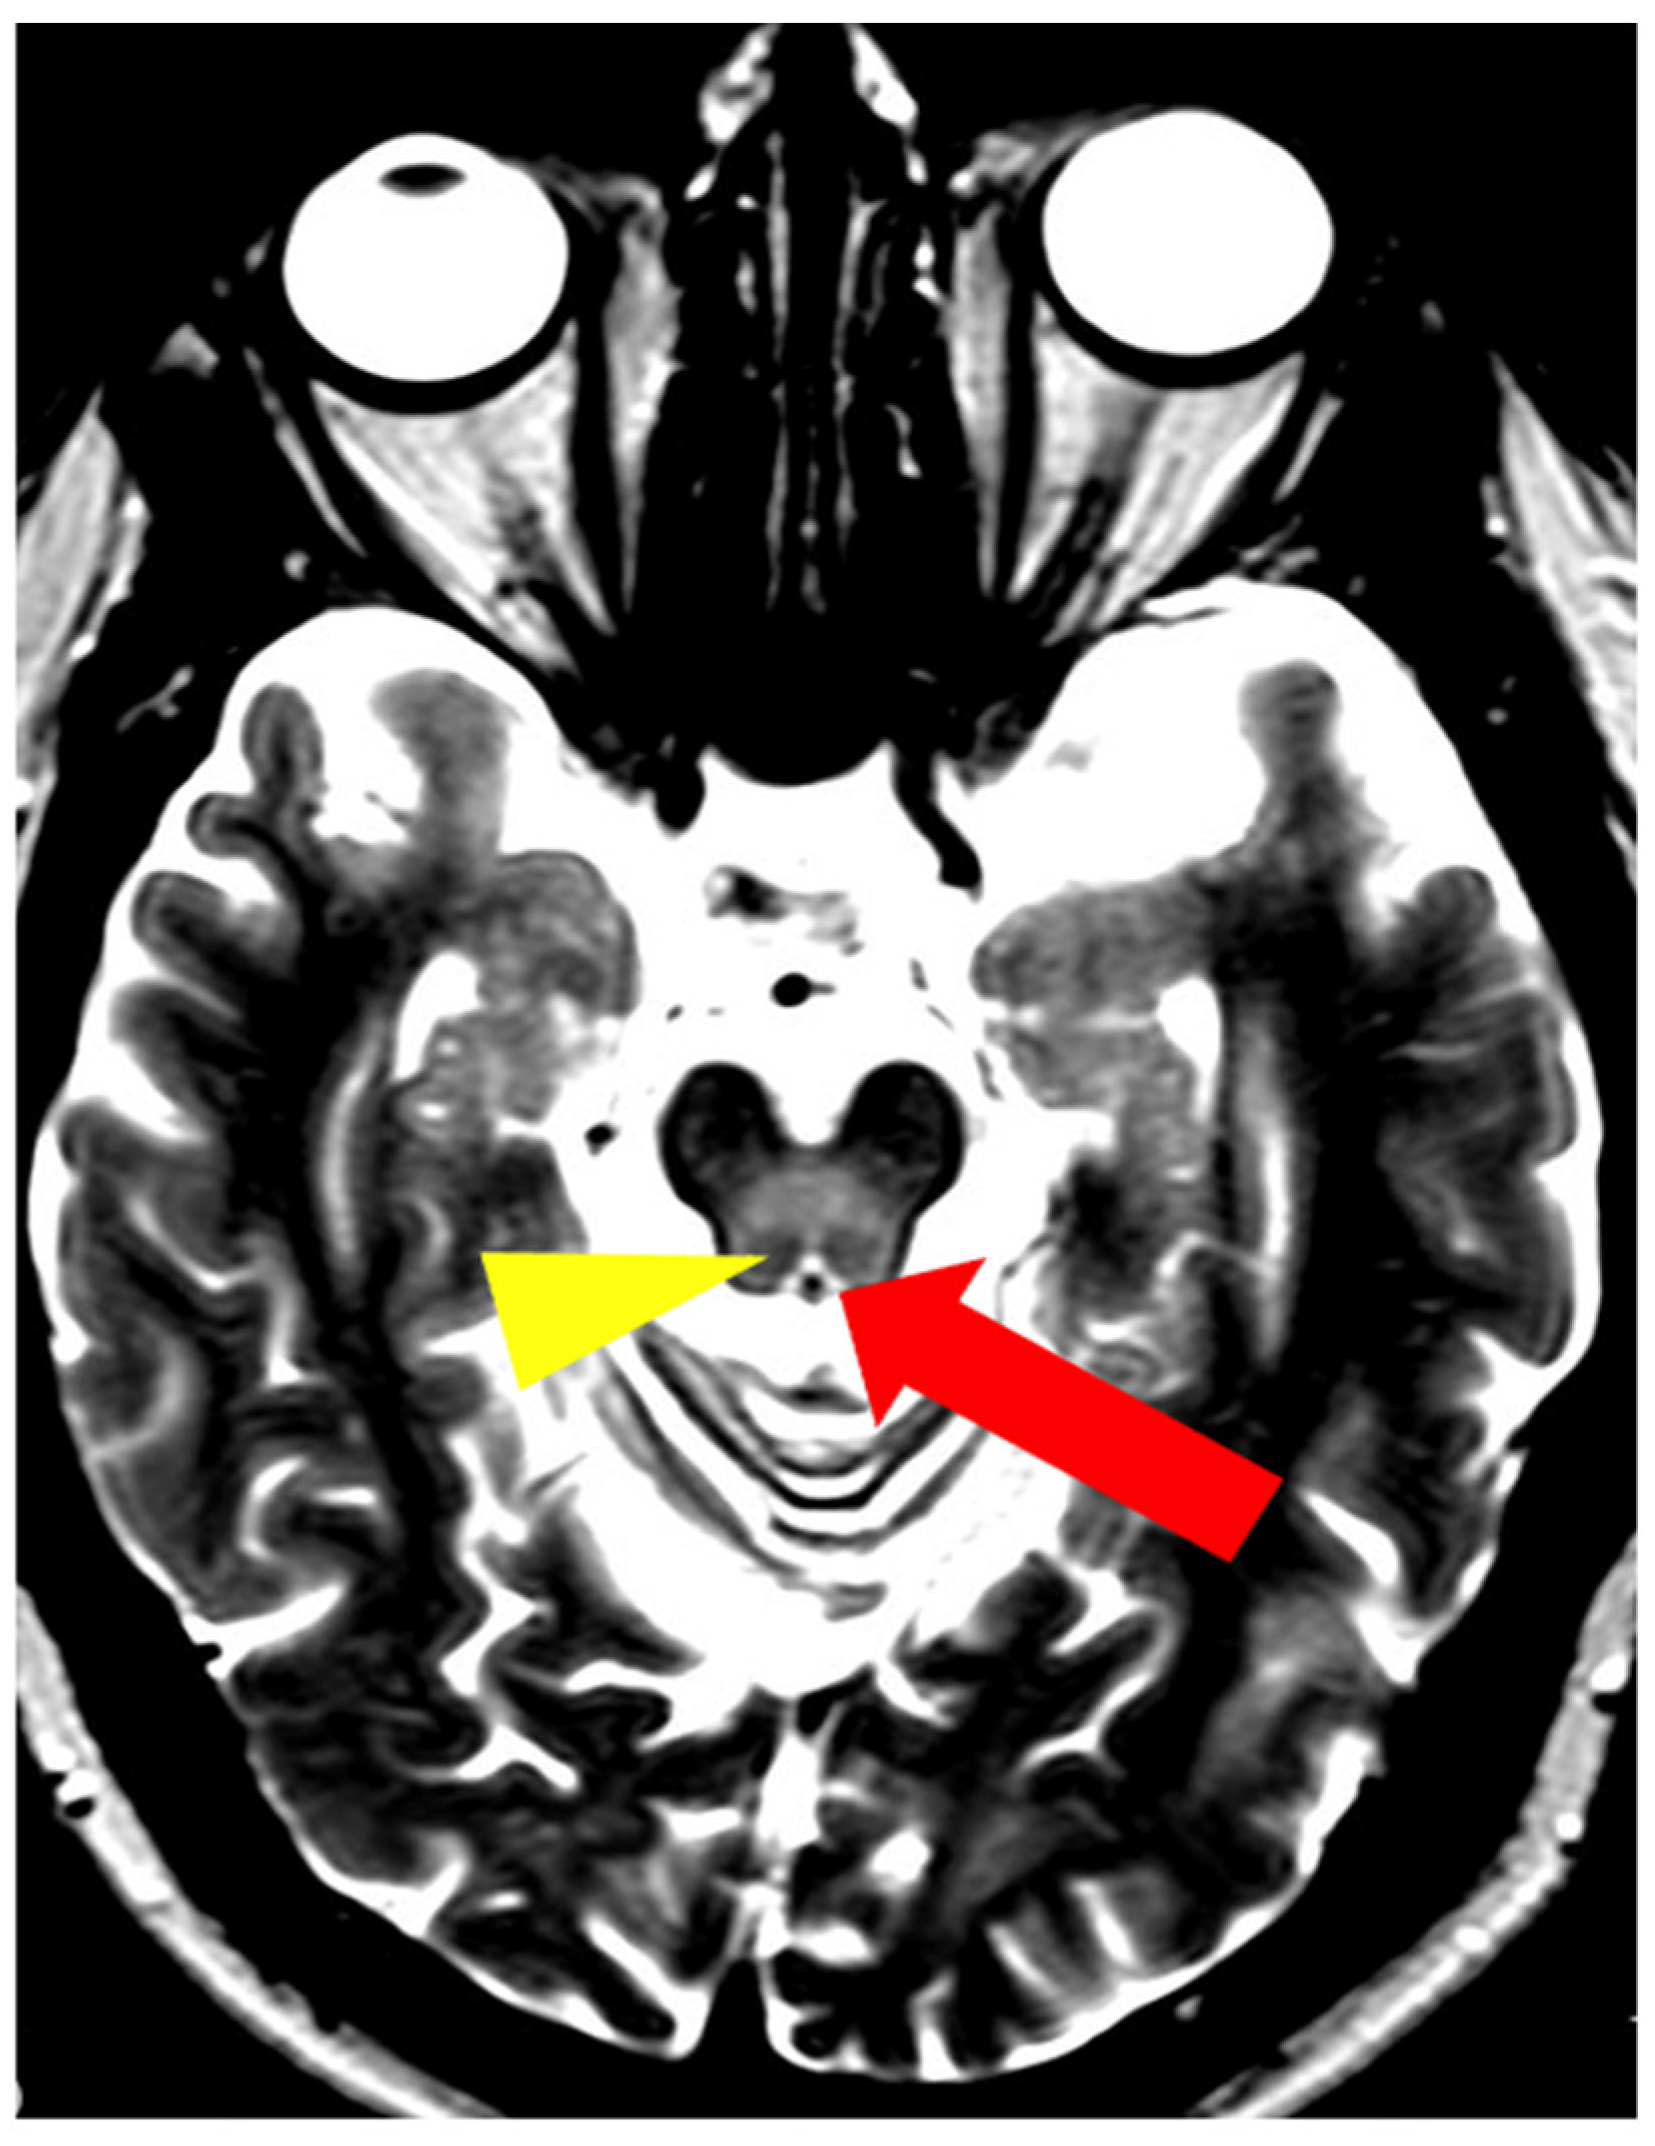

In addition to typical and frequently encountered features among patients with WD, especially in its neurological form, hyper- and hypointense changes in deep brain structures in T2, T2*, FLAIR, and SWI sequences on brain MRI have been noted [10]. Hyperintense foci in the midbrain and pons may sometimes occur in a characteristic pattern with normal brain tissue. Characteristic signs include the ‘face of the giant panda’ in the midbrain and the ‘miniature panda’ sign in the pons, which are considered so-called pathognomonic neuroradiological signs of WD. Besides the aforementioned abnormalities, other pathognomonic signs in WD include the bright claustrum sign, split thalamus (onion sign), and whorl sign [71].

The ‘face of the giant panda’ sign is characterized by an area of increased signal intensity in the midbrain tegmentum and hypointense red nuclei (panda’s eyes), the substantia nigra forming a reticular structure (panda’s ears), and hypointense signal in the superior colliculi (panda’s chin) (Figure 7) [71,72]. The ‘miniature panda’ sign is observed in the pontine tegmentum and consists of hypointense medial longitudinal fasciculi and tegmental tracts (panda’s eyes), hyperintensity of the aqueduct opening into the fourth ventricle (panda’s nose and mouth), with the superior cerebellar peduncles forming the panda’s cheeks (Figure 8) [71,72]. It may appear independently or in conjunction with the ‘face of the giant panda’ sign. In T2 and FLAIR sequences, the presence of a hyperintense internal medullary lamina between the medial and lateral groups of thalamic nuclei has been noted—the split thalamus sign arises from the internal medullary lamina system with significantly increased signal intensity separating the medial and lateral thalamic nuclei with higher signal intensity but lower than the internal lamina (Figure 9) [73]. The whorl sign arises in the putamen due to the coexistence of several concentrically arranged hyperintense bands [15] (Figure 10). The bright claustrum sign arises from the increased signal intensity in the claustrum [74] (Figure 11). In the publication by Su et al., another neuroradiological sign was presented using 7T SWI brain MRI. The hyperintense globus pallidus rim sign was defined as a linear pseudohyperintense signal at the lateral border of the globus pallidus, resulting from the hypointense signal of the globus pallidus and putamen [75].

Figure 8.

The ‘miniature panda’ sign—decreased signal intensity in the medial longitudinal fasciculi and tegmental tracts (arrowhead), hyperintensity of the aqueduct opening into the fourth ventricle (arrow) (own materials of the neurology department).